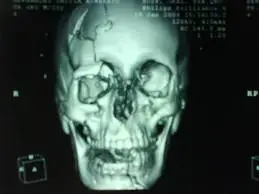

FRACTURA CON HUNDIMIENTO:

FRACTURA HUNDIMIENTO

Es aquella en la que la tabla externa se hunde por debajo del límite anatómico de la tabla interna.

DIAGNÓSTICO: TAC craneal.

TRATAMIENTO: Reparación quirúrgica.